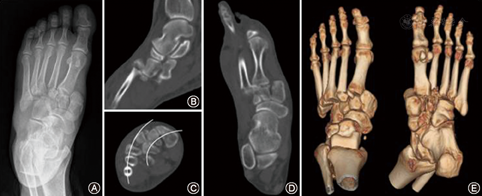

德国西门子64排或美国GE16排多层螺旋CT机行足部扫描,扫描时足处于中立位,定位像从足尖至踝上,扫描范围23~26 cm,同时行5 mm厚层扫描及2 mm薄层扫描,获得薄层横断位后,以第2跖骨的基底部同楔骨形成的关节为基础,行足冠状位、矢状位二维图像重建;行足三维立体图像重建。

Lisfranc关节骨折在CT图像上检出率为100%,骨折累及第2~4跖骨(M2~M4)基底部的患者占63.4%(83/131),累及M2基底部者占87.8%(115/131),M2外侧脱位者占64.1%(84/131)。57例X线片上存在Fleck征,其中52例行CT检查,CT图像上的小骨片71.2%(37/52)来源于M2基底部内缘,23.1%(12/52)来源于M1基底部外缘,5.8%(3/52)来源于内侧楔骨外缘。以M2的基底部同楔骨形成的关节轴线重建的冠状位及矢状位可清晰显示榫眼关节的结构、Fleck骨片来源、关节脱位方向。足弓扁平的患者在CT横断位上可观察到M1~M5排列的弓桥样结构消失,显示以M2骨基底部为基础的排列紊乱。此外,CT三维重建观察到背侧脱位和半脱位患者37.4%(49/131),跖侧脱位和半脱位患者7.6%(10/131)(图4),M1~M5中部分跖侧脱位,部分背侧脱位患者1.5%(2/131)(图4)。